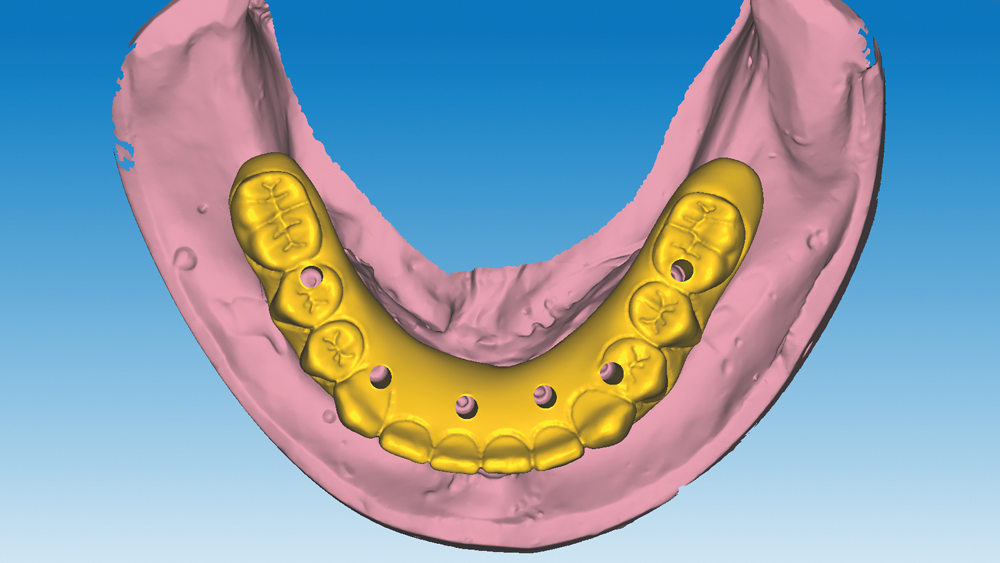

This patient was unhappy with the esthetics of her existing upper denture as well as the discomfort and instability caused by her loose-fitting mandibular partial denture. Although her concerns with the maxillary denture could be addressed with a new, more esthetic appliance, she preferred implant treatment for her mandible, where a fixed solution was needed to adequately restore function, stability and comfort.

Treatment plan:

The patient’s remaining mandibular teeth were extracted followed by immediate implant placement and delivery of a fixed provisional appliance. After integration of the implants, the prosthetic designs for the new upper denture and lower implant restoration were determined in tandem. Ultimately, the dual-arch restorations addressed the functional and esthetic challenges of the case while staying within the financial means of the patient, demonstrating the benefits of a flexible, multifaceted approach to restorative dentistry.